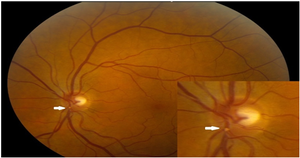

العلامات المزمنة لانسداد الشريان الشبكي تتضمن : قرص بصري شاحب , ترقق في أنسجة الشبكية , أوعية مستدقة ,تبقع في الظهارة الصباغية للشبكيه , نقص رؤية شديد .

إن نقص الرؤية المرافق للCRAO عادة ما يكون شديد , وهو على صلة وثيقة بمقدار الوذمة في الشبكية . وعلى الرغم من ذلك فإن ال CRAO المترافق مع شريان شبكي هدبي سليم فإن القدرة البصرية يمكن أن تتحسن الى 20/50 أو أفضل من ذلك في 80% من العيون .

إن التوعي الشبكي الحديث غير شائع ولكن يمكن أن يحدث وعندها يجب متابعة المرضى بشكل وثيق . يجب فحص ومتابعة المرضى لتحري أي توعي قزحي حديث والذي سجل نسبة حدوث حوالي 2.5% الى 31.6% من المرضى .

وأخيرا هناك دراسة حديثة بينت انتشار التوعي حوالي 18%بمتوسط بداية بعد 8.5 أسبوع من الانسداد .